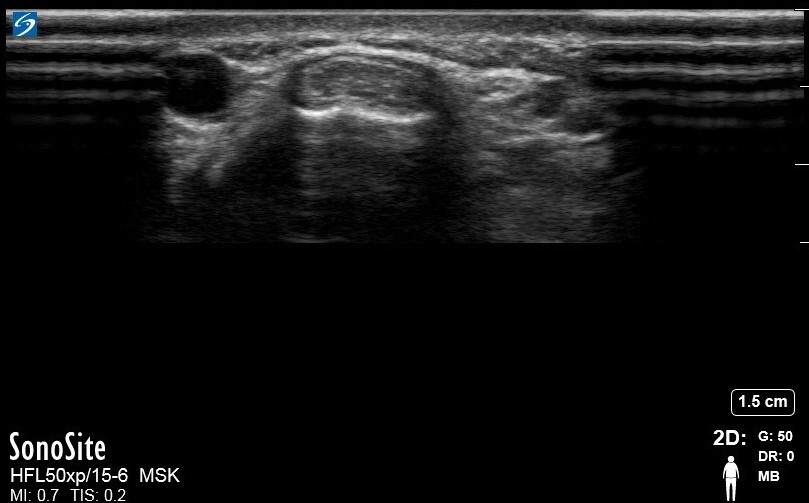

Wrist Abductor Pollicis Longus and Extensor Pollicis Brevis 3 Image